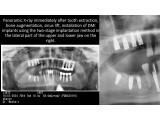

Direct implantation with immediate loading & FOLLOW-UP 7 YEARS AFTER SURGERY

Clinical case: Direct implantation with immediate loading, bone augmentation, sinus lifting and soft tissue monitoring. Follow-up 7 years after surgery

Dentist: DDS PhD Ilia Mushayev/Sidhedent, DMi (Israel)